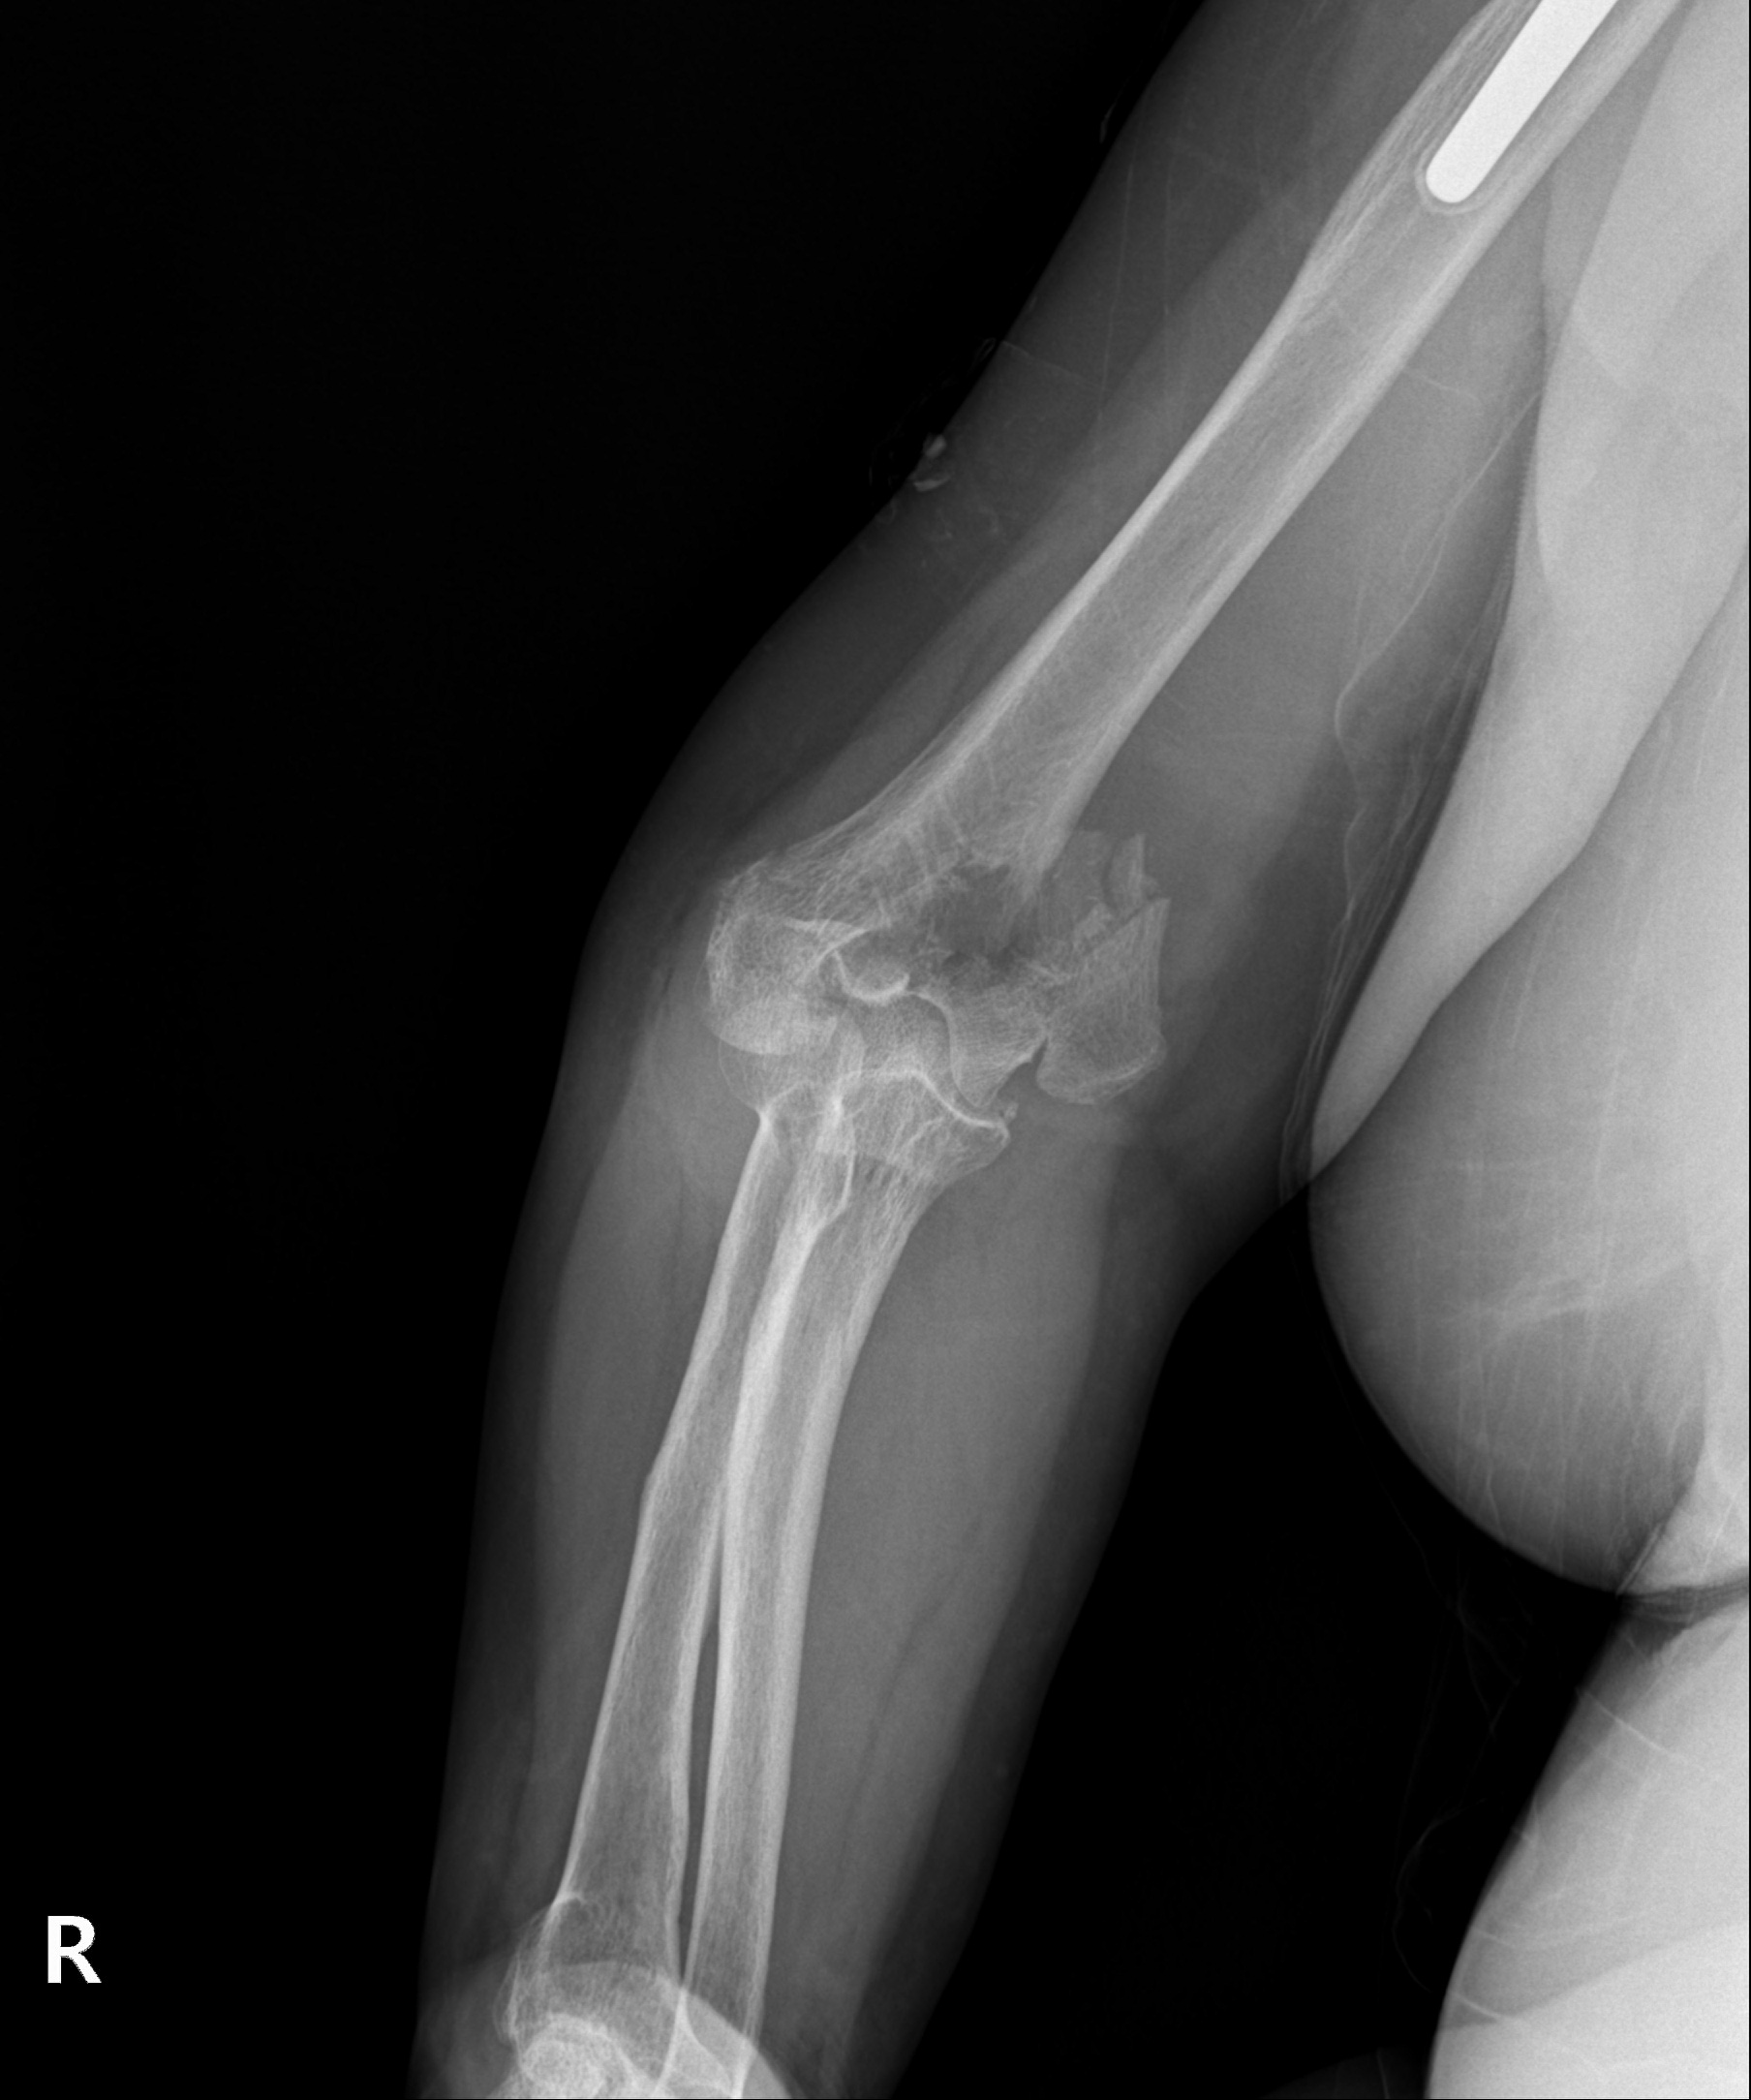

원위 상완골 골절

2022.07.14

2023.02.07